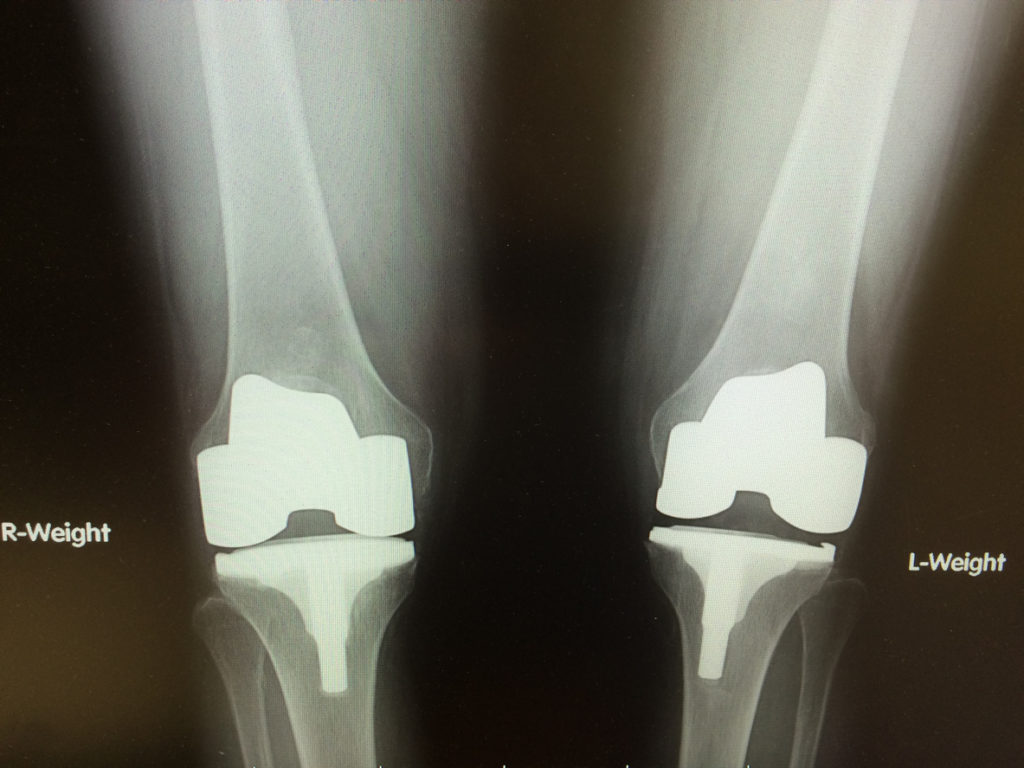

Full Knee Replacement Surgery

Total knee arthroplasty is the full replacement of the knee joint. It is performed by making surgical adjustments to the bottom of the femur, the top of the tibia, and the kneecap, and replacing them with a prosthetic knee joint. The prosthesis is generally made of metal alloys, titanium, and medical-grade plastics.